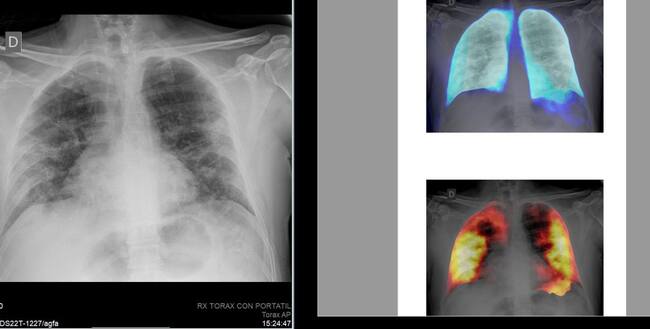

El proyecto se basa en la inteligencia artificial para mejorar los diagnósticos por Covid / Fisabio

El desafío científico, que se llevará a cabo a través de la plataforma Kaggle, utilizará conjuntos de imágenes de radiografías convencionales de la Medical Imaging Data Resource Center (MIDRC) - RSNA International COVID-19 Open Radiology Database (RICORD) y del BIMCV-COVID-19 Dataset (Banco de Imagen Médica de la Comunidad Valenciana). El dataset fue entregado en formato MIDS (Medical Imaging Data Structure).

Todas estas bases de datos de imágenes han sido anotadas (etiquetadas para que los modelos de Inteligencia Artificial puedan aprender correctamente) por un grupo internacional de radiólogos voluntarios de Brasil, EE.UU y en España del Hospital Sant Joan de Alicante cuyo responsable es el Dr. Joaquín Galant Herrero.

Las personas participantes en el desafío desarrollarán modelos de computación de alta calidad para detectar y localizar la neumonía por la COVID-19 para ayudar a los médicos a proporcionar un diagnóstico rápido y seguro que mejorará la atención del paciente al permitir un tratamiento adecuado antes de que aparezcan los efectos más graves del virus.